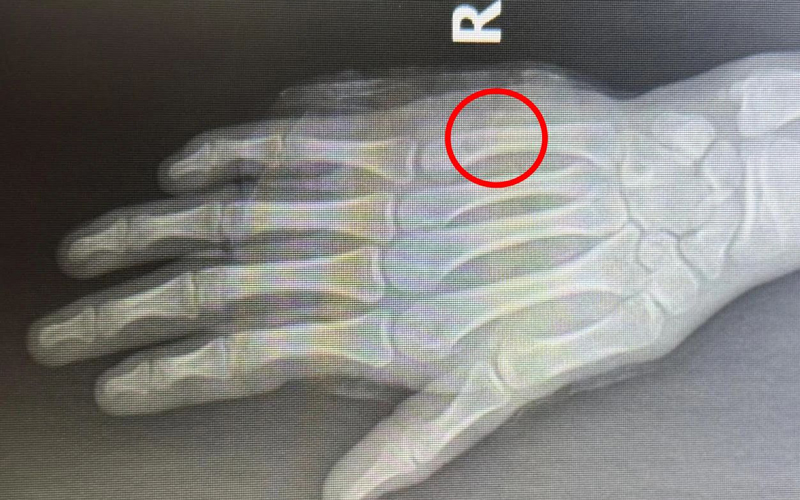

患者小徐今年16岁,因在学校不慎撞伤导致右手肿痛难忍来院就诊,穆中杰教授与科室医生认真研判病情,考虑患者为掌骨骨折可能,经过检查显示右手第5掌骨颈骨折,又称“拳击手骨折”,是临床上比较常见的手部骨折。

同患者及其家属进行沟通,决定行手法复位+杉树皮夹板固定,同时使用金黄散外用消肿止痛治疗,复位后骨折基本达解剖复位,患者及家属十分满意。

遂再次就诊于我院,经穆教授手法复位后,检查显示骨折复位良好。